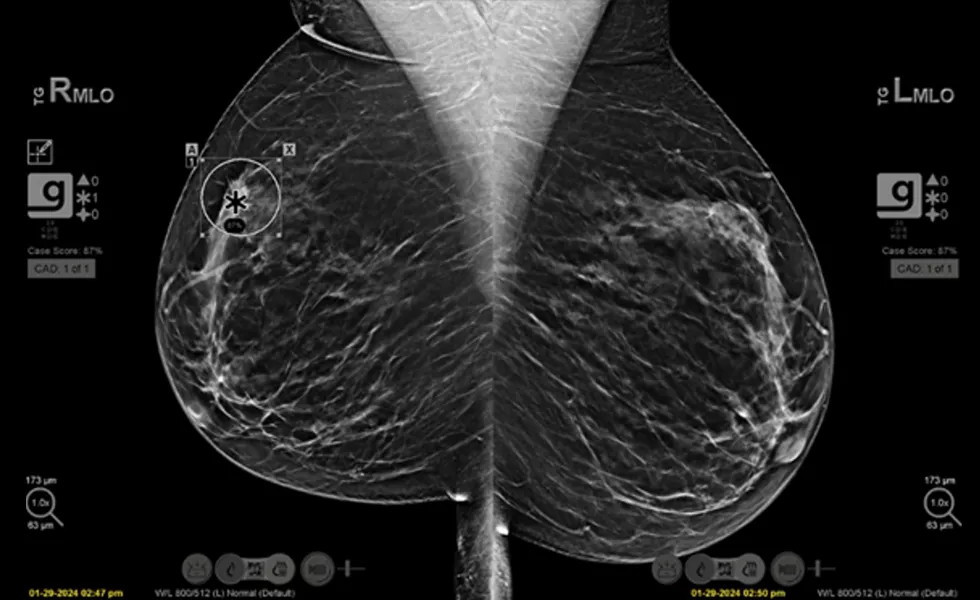

X-ray image

As published in the clinical review, the left image view shows no abnormalities bilaterally, while the right image reveals an area of concern marked by the Genius AI Detection, with a case score of 87% and flagged as high priority.